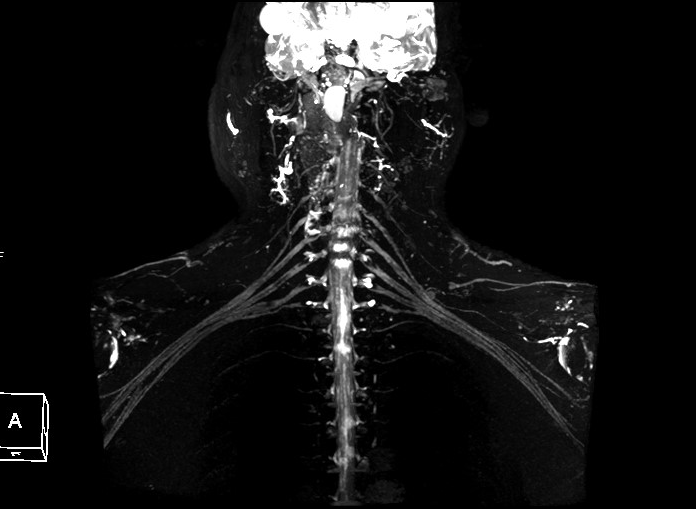

八、神经臂丛成像:此项检查技术在临床中主要应用于外伤患者有无神经丛的损伤。

联影磁共振怎么样平原县第一人民医院联影uMR780 光梭3.0T磁共振正式投入使用,开启医学影像新时代!_https://www.jmylbn.com_新闻资讯_第24张

联影磁共振怎么样平原县第一人民医院联影uMR780 光梭3.0T磁共振正式投入使用,开启医学影像新时代!_https://www.jmylbn.com_新闻资讯_第25张